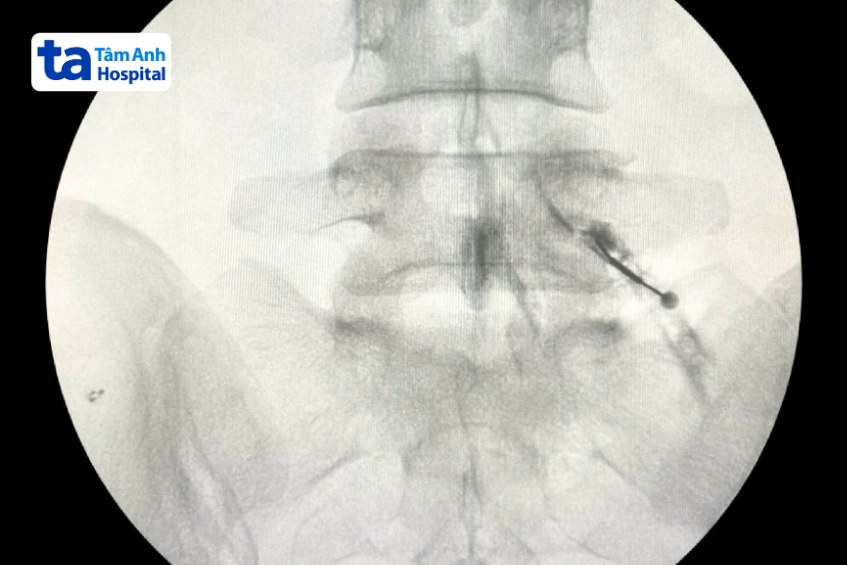

Trường hợp của chị Kiều, bác sĩ thực hiện tiêm hoạt chất gồm thuốc tê và steroid vào xung quanh rễ thần kinh đang bị chèn ép và viêm. Tất cả các thao tác được thực hiện dưới sự giám sát của hệ thống chụp X-quang liên tục C-Arm, đảm bảo đưa thuốc tiếp cận đúng rễ thần kinh và phát huy tác dụng nhanh chóng.